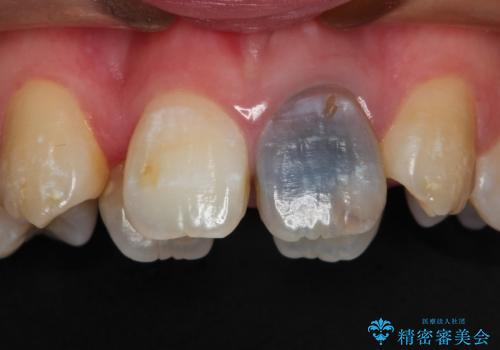

前歯が黒い セラミックで綺麗に 20代女性